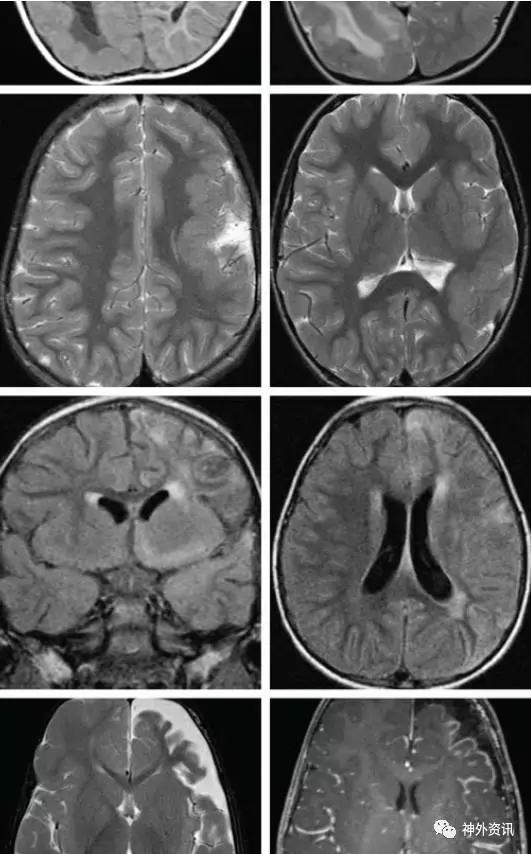

图1. 显示为右侧中等程度的半侧巨脑症。弥散性的皮层发育异常(最上图);注意脑室周围的变化;异位的灰质被发现在脑室周围;这些异常的变化在后半球尤为明显。第二排图显示:左侧外侧裂周围区的脑回增厚。第三排图显示与左侧相符合的Rasmussen’s脑炎的影像学表现,同时为手术活检证实;T2相显示异常者为脑组织的萎缩。最下图显示了Sturge-Weber综合征的影像学表现:左侧额颞叶的萎缩、枕叶软脑膜的增厚和枕极增强表现,提示血管病变。